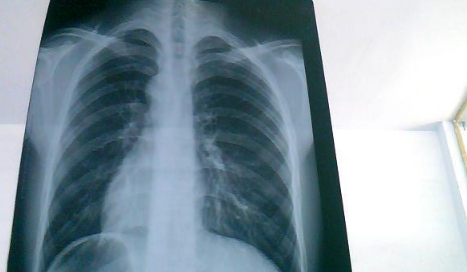

白肺是目前很常见的情况,受新冠影响很多老年人都出现了白肺的情况,当然也有年轻人会患上白肺。那么,如何自查是否出现白肺?平时怎样保护自己的肺?一起来看看中睿百科网带来的详细介绍吧!

如何自查是否出现白肺

如果出现白肺,患者可能会出现一些严重的呼吸道症状,包括咳嗽、喘息、呼吸困难或体力活动时呼吸短促。一个更客观的指标是病人的呼吸频率,通常大于每分钟30次呼吸,或血氧饱和度低于93%就要警惕出现严重肺部感染。白肺并不能预防,只能预警。

肺白了还能恢复吗

肺白了一般是指白肺,白肺能否恢复与疾病类型、严重程度有一定关系,有些患者在检查时,发现肺白密度增高,如果是轻度肺部炎症引起的白肺一般是可以恢复的,如果是严重肺部炎症或肺间质纤维化引起的,则可能无法恢复。

如果是比较严重的肺炎或肺间质纤维化引起的白肺,一般会伴有呼吸困难的症状,首先应该改善患者的呼吸状态,可以帮助患者通过吸氧呼吸,也应该使用抗生素类药物进行治疗,症状消退后,白肺症状会相应减轻,但一般不会完全恢复。

此外,白肺也可能由肺结核、肺肿瘤等原因引起,需要鉴别诊断。